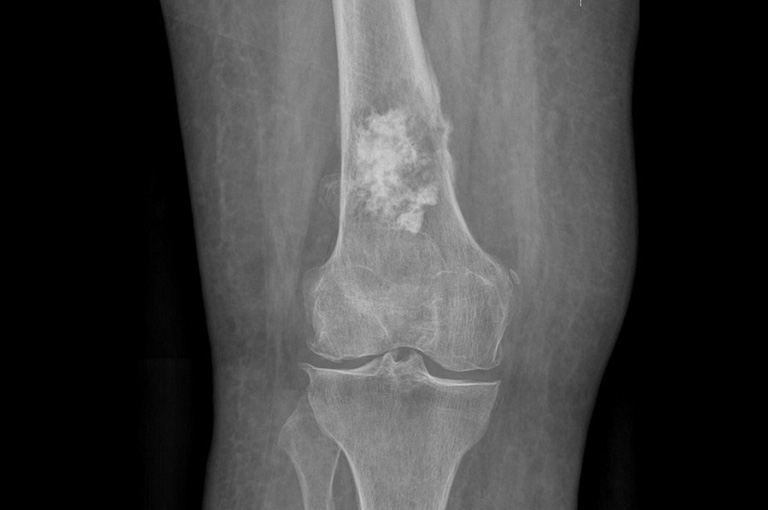

- Chụp CT là phương pháp sử dụng các tia X-quang tạo ra hình ảnh chi tiết bên trong cơ thể bạn. Chúng giúp bác sĩ phát hiện ung thư và xem liệu nó có di căn sang các khu vực khác hay không.

- Kết quả chụp X-quang chỉ ra vị trí, hình dạng và kích thước của khối u.